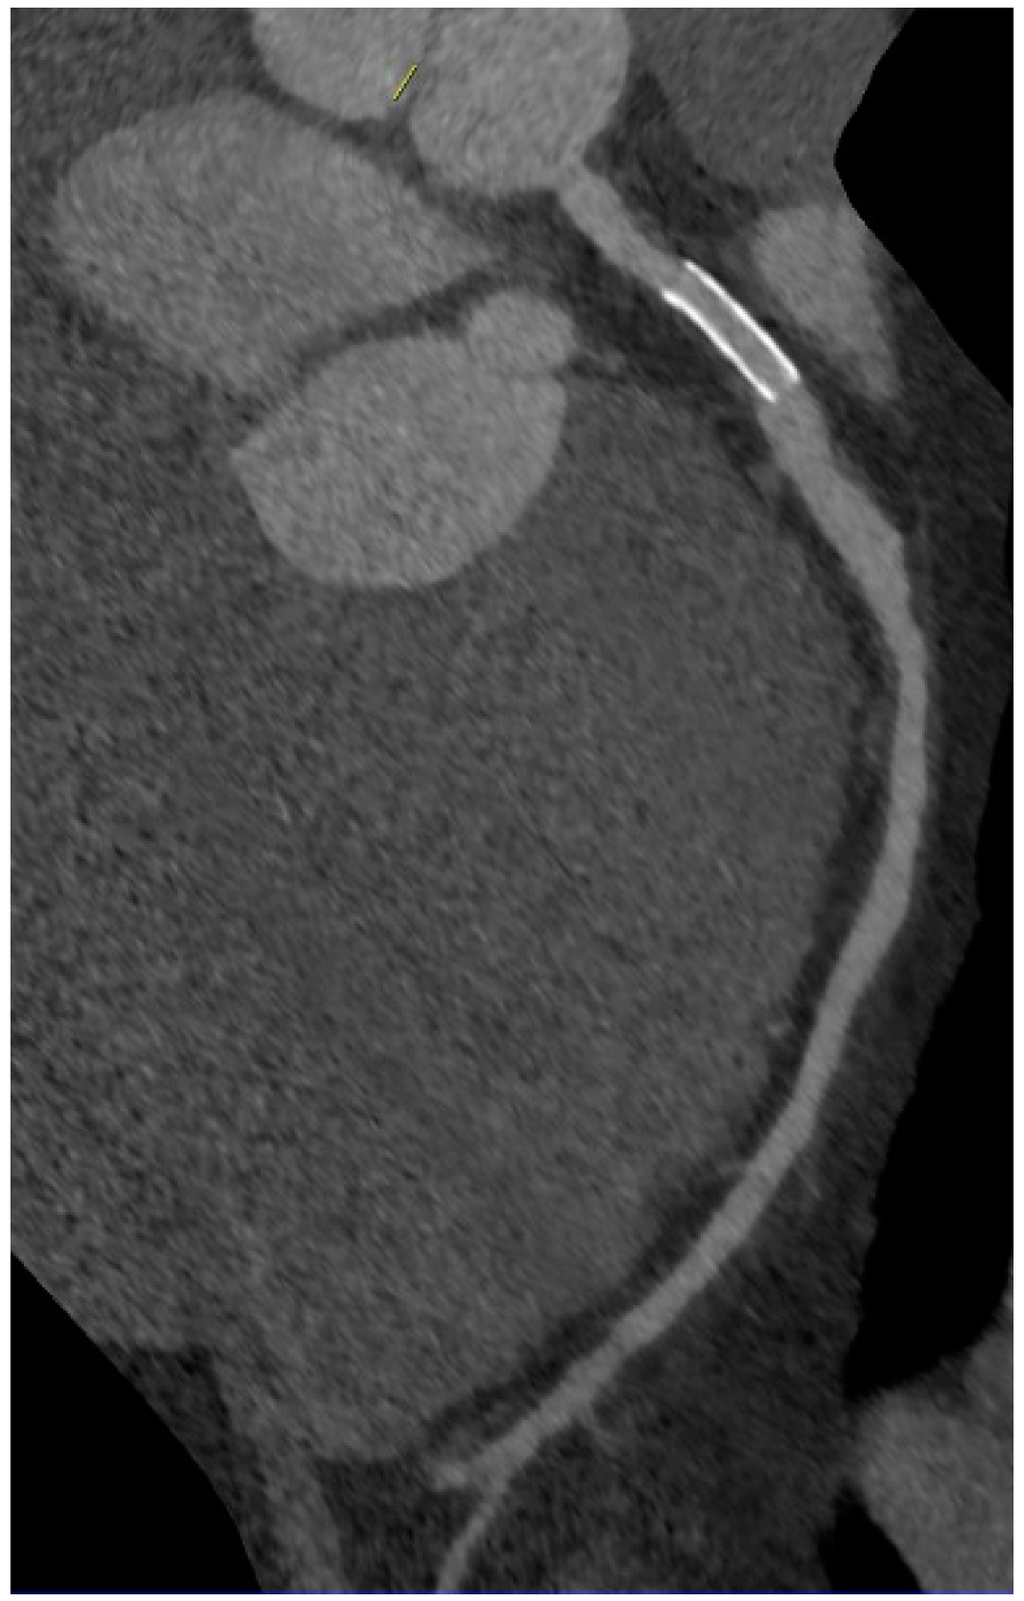

5. Coronary CT Angiography

6. Imaging of Coronary Plaques and Stenoses